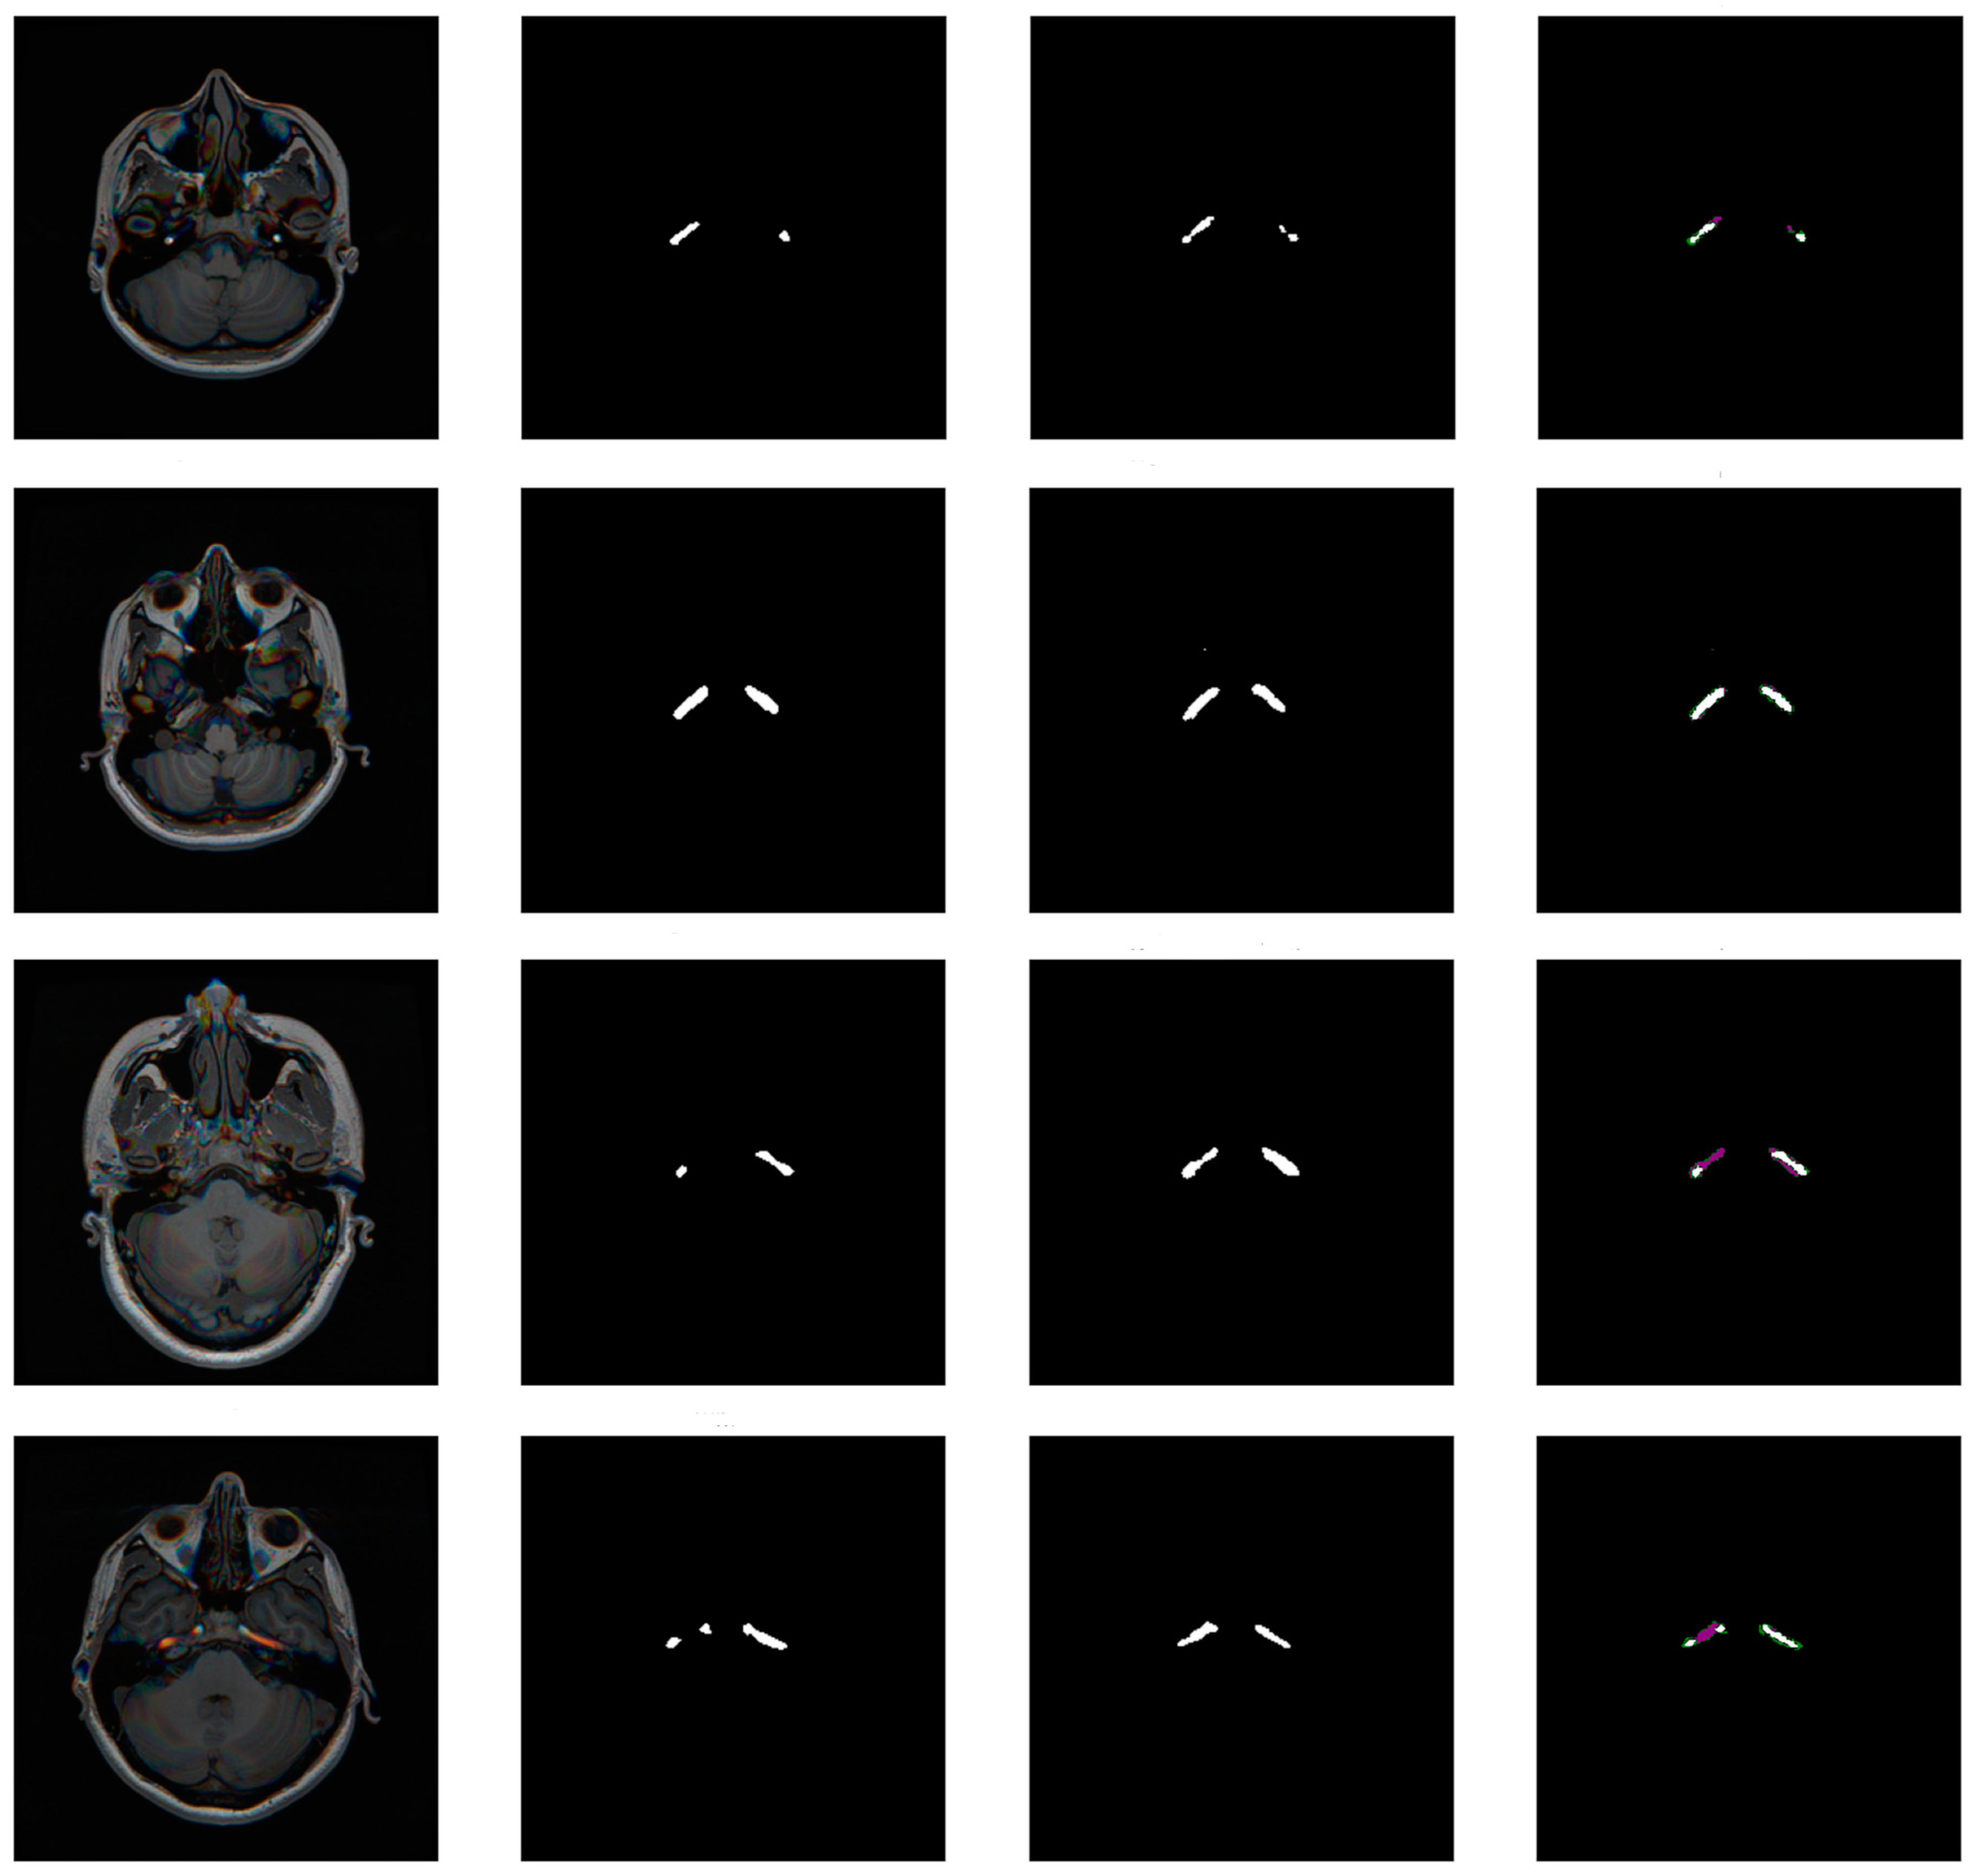

- We first train five models with the bounding boxes as the target for the semantic segmentation using 5-fold cross-validation (Round 0). We stratify the fold so that each fold has the same dataset separation. The model is trained for a maximum of 100 epochs. The training stops if the network does not improve the validation’s mean Intersection over Union (IoU) [34] in 10 epochs. We also only save the best weights in the validation.

- We used the trained models in an ensemble (average of the five cross-validation models’ predictions) to perform the segmentation in all the training dataset images, including those used to train them. After, we post-process the predictions using an erosion morphological operation, with a disk of radius one as the structuring element. This operation was performed only during the first four training rounds to eliminate a bit more of the false positives that naturally occur because of the initial bounding boxes.

- Using each post-processed mask, we calculate the IoU for the bounding boxes: if it is above 50%, we use the prediction of the post-processed mask as a new mask. If not, we return to the initial bounding box as a mask. We calculate the IoU for each carotid, separating the images into two parts, evaluating the image for each artery separately, and concatenating the results.

- Finally, we multiply the resulting mask by the bounding boxes, erasing pixels outside them.